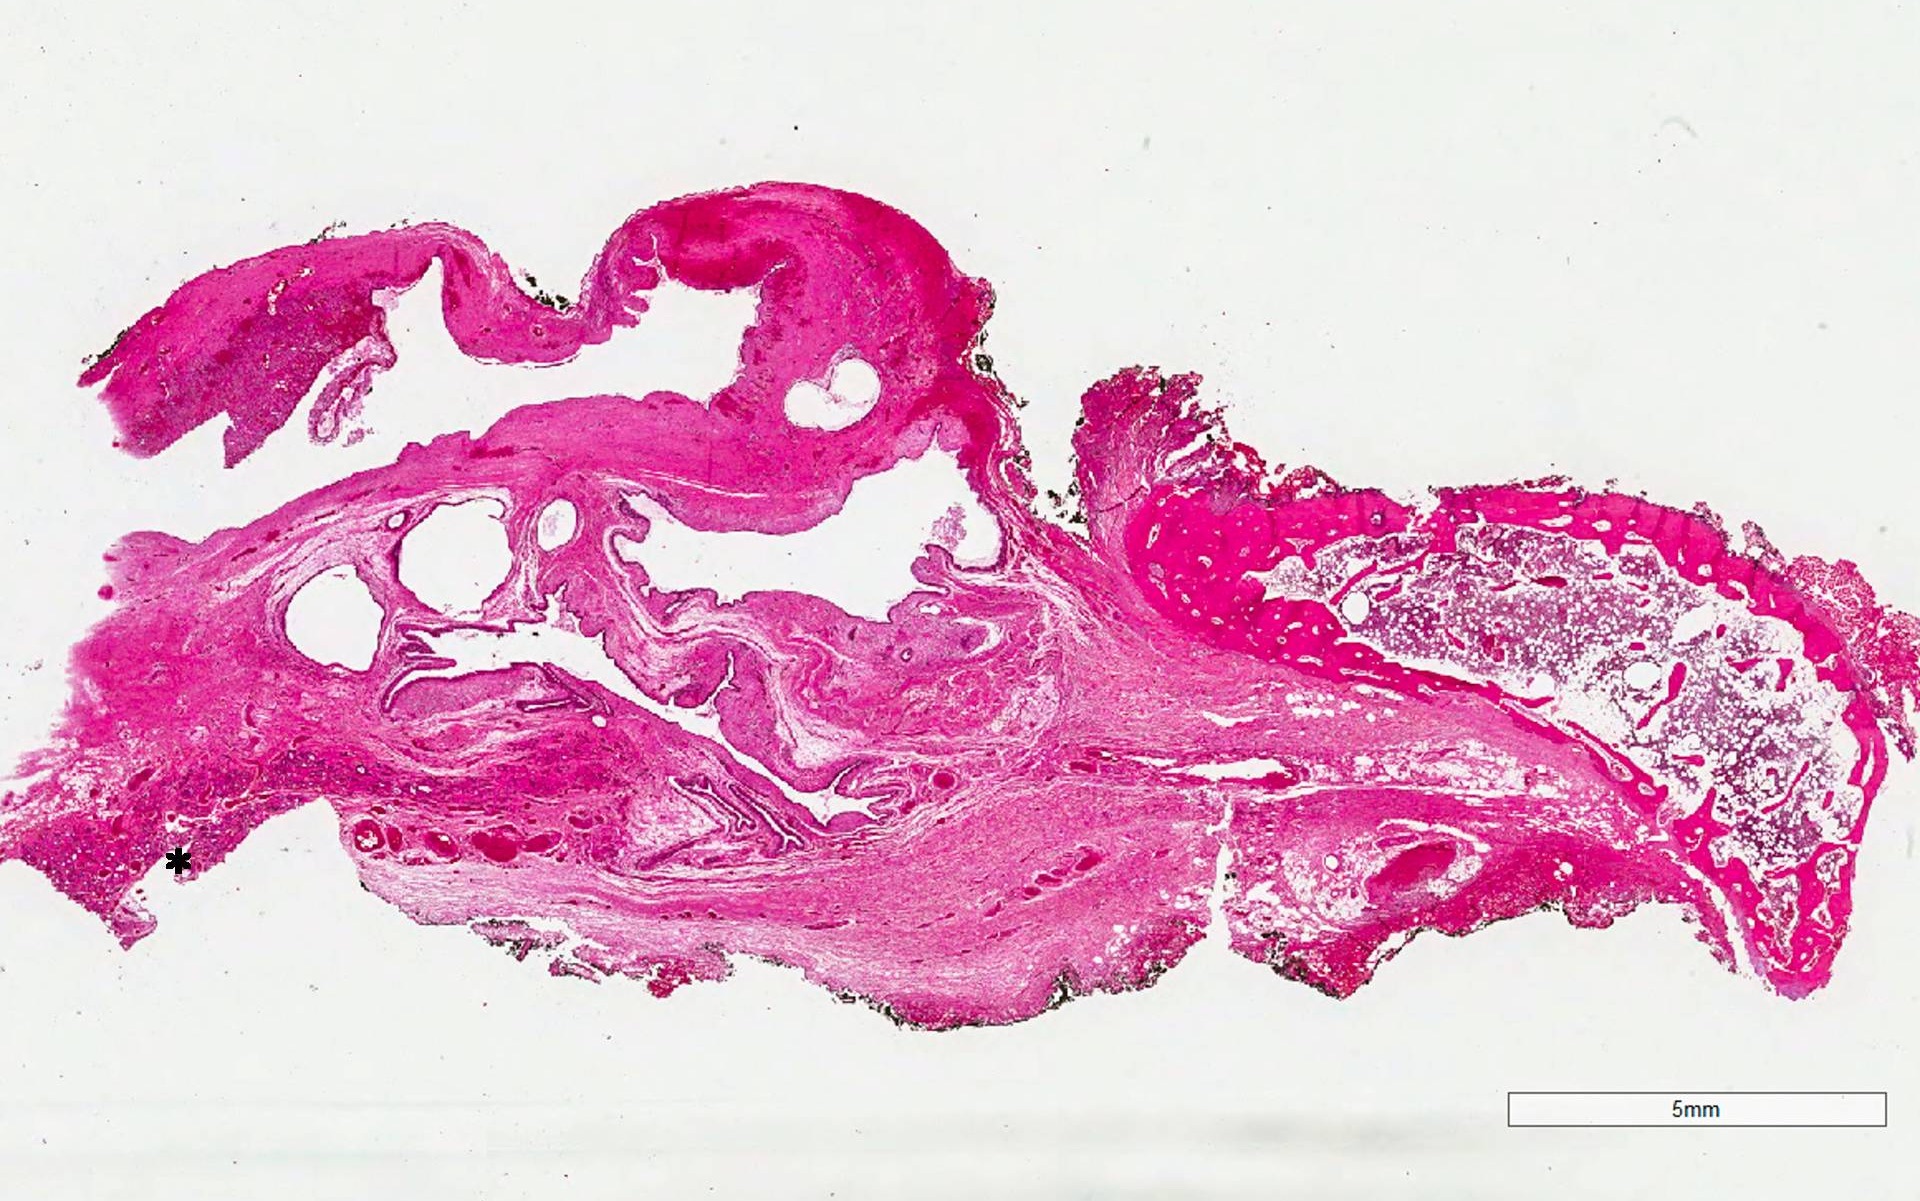

Microscopic (histologic) description

- Type of epithelial lining varies by site, and combinations of the types below can be seen in a single cyst (Head Neck Pathol 2013;7:50):

- Ciliated pseudostratified columnar (respiratory) epithelium in lower neck, perhaps due to its close proximity to upper respiratory tract

- Nonkeratinizing squamous epithelium in higher neck (near tongue and foramen cecum), also can be of metaplastic origin in inflammatory settings

- Stratified cuboidal epithelium at level of hyoid bone

- Very often the cyst is denuded of epithelium, at least focally, which reflects epithelial damage by inflammation

- Secondary inflammation is common, especially in sinus tract (J Pediatr Surg 1984;19:506):

- Intense lymphocytic infiltration, rarely arranged into lymphoid follicles

- Admixture of neutrophils (if the cyst is infected)

- Granulation tissue and fibrosis

- Thyroid follicles in the cyst / duct wall:

- Found in 30% - 60%, with higher yield on serial sections

- More common in infra- versus suprahyoid remnants, on the right paramedian side (Ann Otol Rhinol Laryngol 2000;109:1135)

- Seen in small irregular groups

- Thyroid epithelium may be normal or rarely hyperplastic or neoplastic

- Thyroid tissue often hidden by inflammation (Laryngoscope 2001;111:1002)

- Absence of thyroid tissue does not exclude the diagnosis of TGD cyst

- Mucous salivary-type glands can be found in the cyst wall, frequently in lingual and suprahyoid locations (Ann Otol Rhinol Laryngol 1996;105:996)